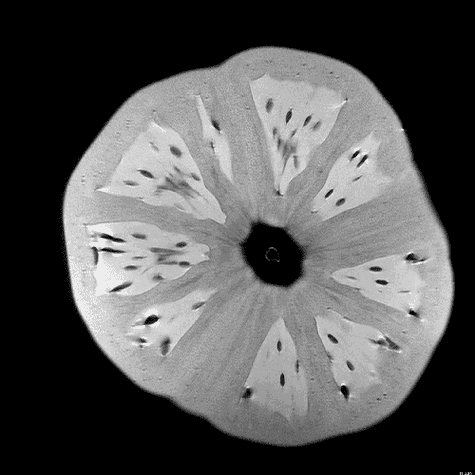

Quizás no sea lo más ortodoxo, pero no podemos negar su componente curioso y llamativo. Seguramente pocos nos imaginaríamos que una fruta de la pasión o la raíz de un apio tienen en su interior un aspecto muy similar al del cerebro. O que las fresas se parecen a un panal de miel. Aclaremos el misterio: esto ocurre cuando las frutas son observadas a través de una resonancia magnética.

Andy Ellison, técnico en resonancias magnéticas del Centro de Imágenes Biomédicas de la Escuela de Medicina de la Universidad de Boston, se ha propuesto enseñarnos de este modo cómo son las entrañas de las verduras y las frutas que comemos a diario. Para ello, ha utilizado la tecnología médica avanzada con la que trabaja para capturar las secciones transversales de estos alimentos, de la misma manera que cada día se hace con el cerebro humano, las rodillas o la columna.

El resultado, que recoge en su blog Inside Insides, son unas fascinantes imágenes y GIFs que nos muestran las frutas y las verduras desde otro punto de vista. Desde un interior tan llamativo y adictivo como lo pueden ser sus colores, formas y sus texturas. La colección es amplia y da para todo tipo de evocaciones, porque por el escáner de Ellison –en concreto, una Philips 3 Tesla MRI, explica– han pasado todo tipo de alimentos, desde los más comunes como las cebollas, los pimientos, los tomates o los plátanos, hasta lichis, la jaca (también conocida como jackfruit, uno de los frutos más grandes del mundo), la fruta del dragón o el kiwano (o pepino africano).